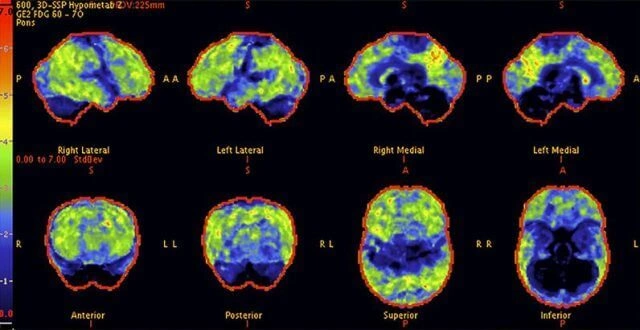

Above: A 68-year-old woman with a 10-year history of cognitive issues. Previous PET scans showed significant metabolic decline, indicating Alzheimer's.

Above: The patient's PET scan after CureFight treatment shows improvement, with cognitive abilities greatly enhanced as the scan approaches that of a normal brain.